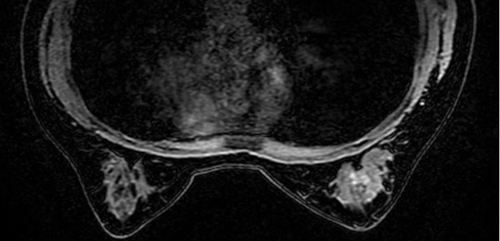

接診專家通過查體和超聲、鉬靶、乳腺磁共振等相關(guān)檢查,發(fā)現(xiàn)孔大姐右乳腺體存在約3.6cm*3.2cm*1.6cm的包塊,病灶邊緣毛糙,右側(cè)腋窩有腫大淋巴結(jié)。專家經(jīng)討論后,認(rèn)為腫塊惡變的可能性極大,一旦擴散轉(zhuǎn)移到身體其他重要器官,可能危及生命。

圖片來源于網(wǎng)絡(luò)